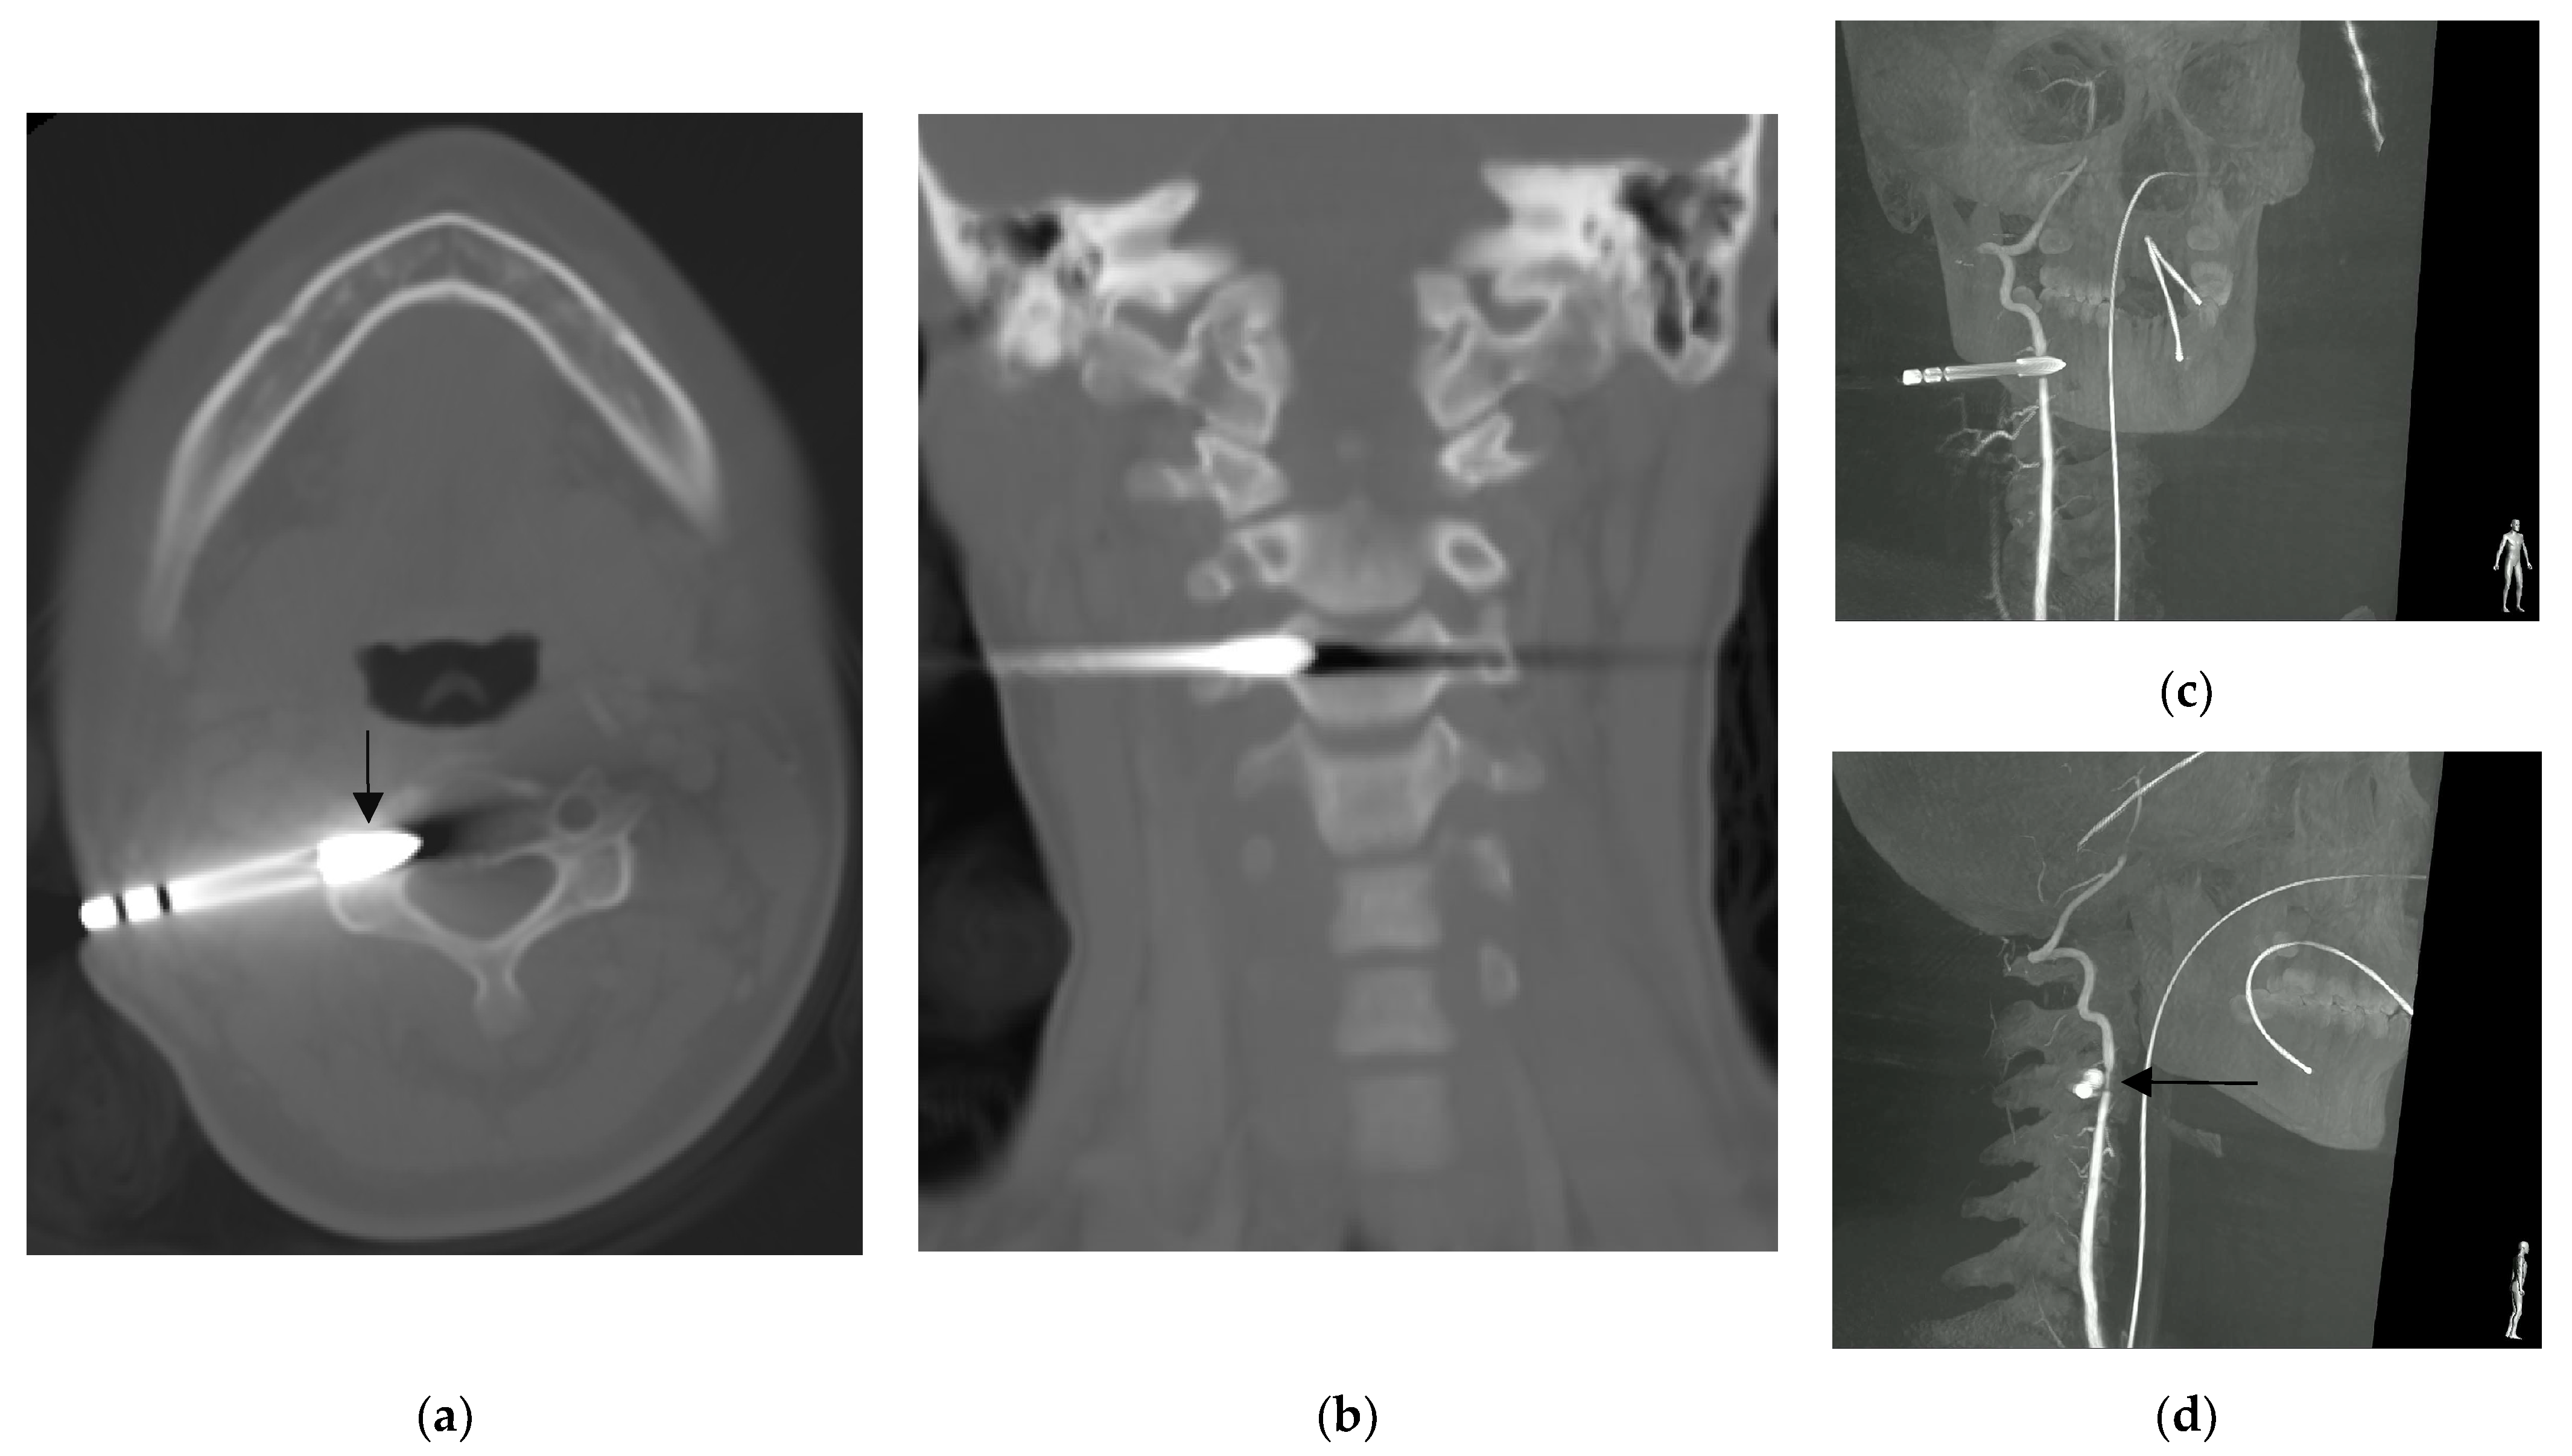

Figure 2.

Computed tomography showing: (a) the arrowhead (arrow) lodged at the transverse foramen of third cervical vertebra without violating the central canal, and; (b) the coronal reconstruction of the same scan showed that the arrowhead did not violate the neural foramen. Right vertebral artery angiography rotation view (c,d) showed narrowing of the right vertebral artery indented by the arrowhead (arrow) [1].